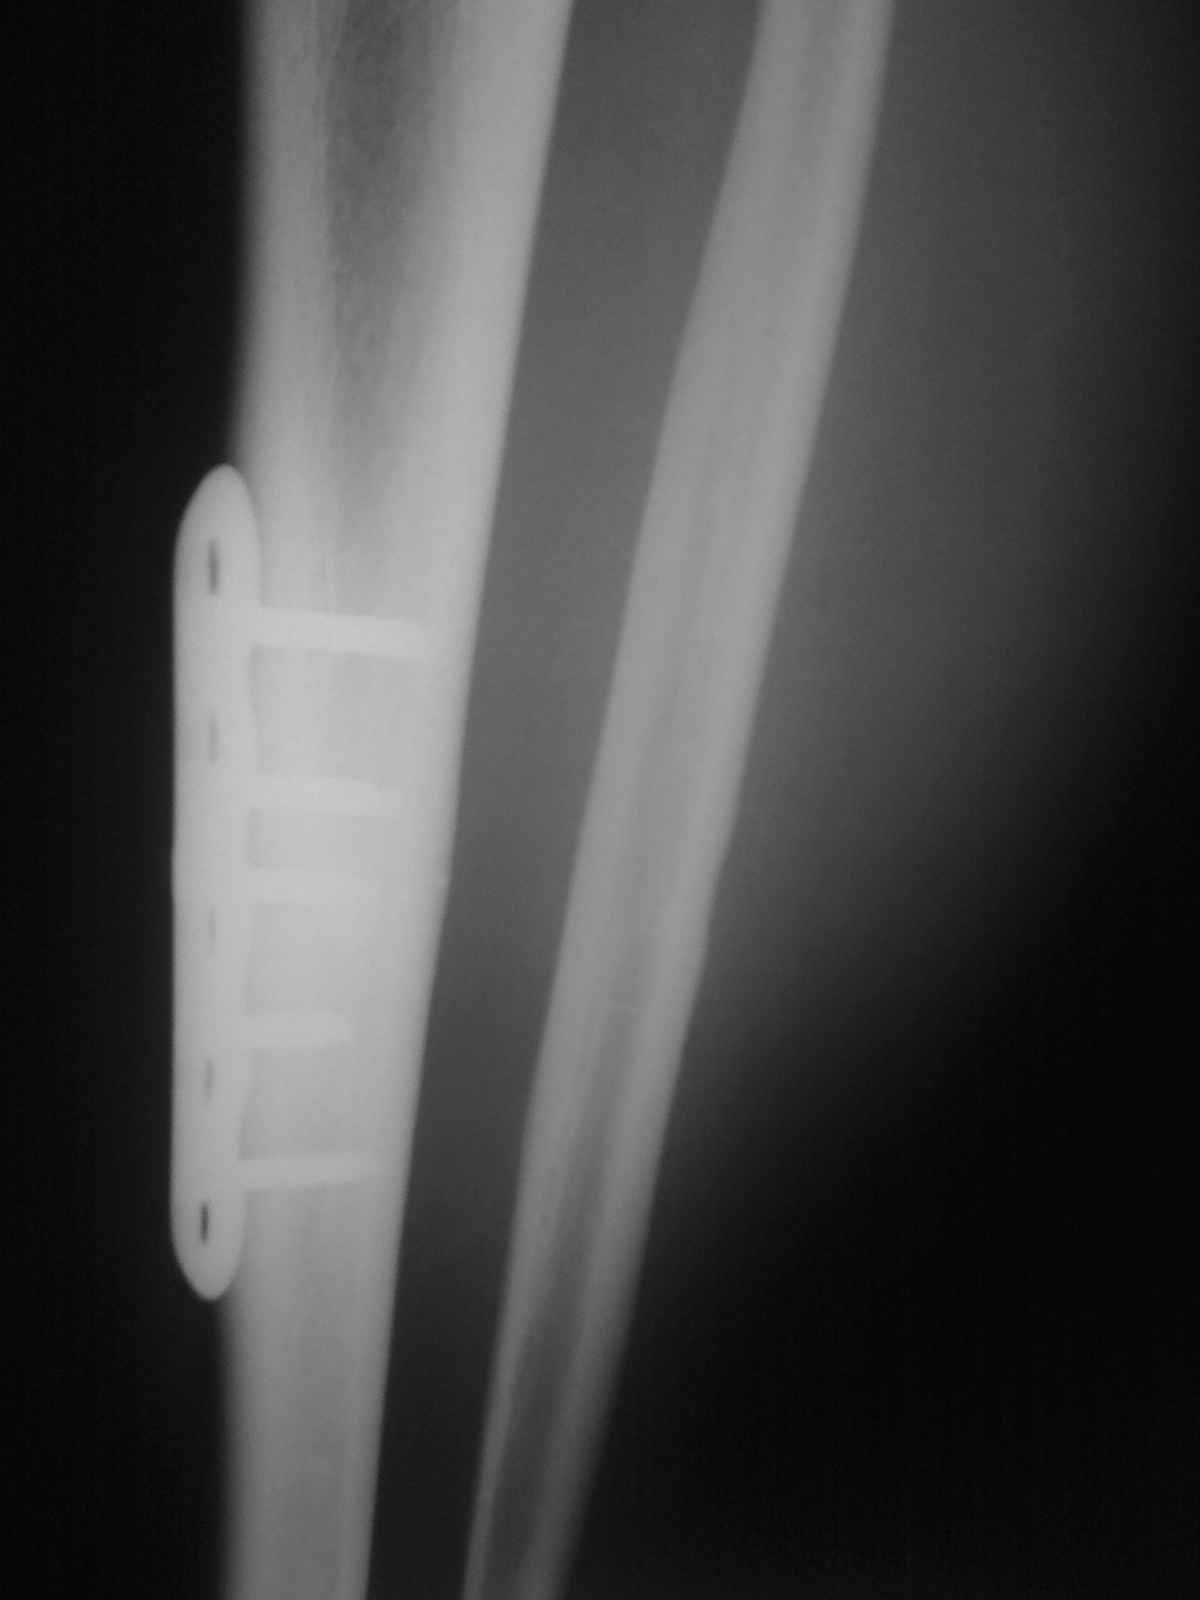

[Ortho] Патологический перелом большеберцовой кости.

Р-гр